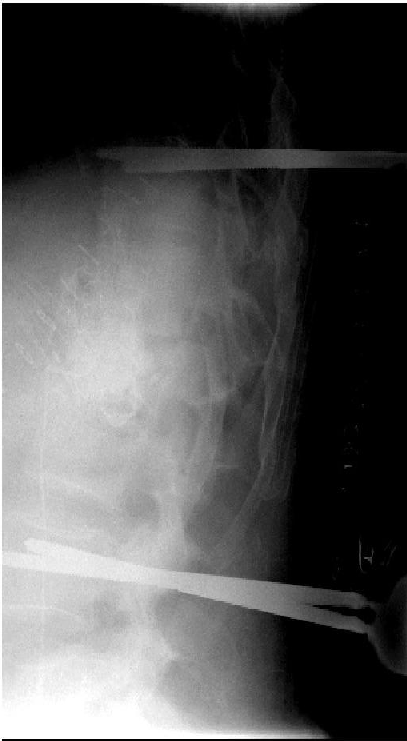

Figure 11. Left: Complete implant removal, radically surgical debridement and external spine fixation with vacuum wound closure (Hoffmann II external fixator, 5.0 mm Pins). Right: X-ray Image of the thoracolumbar spine. External posterior stabilization.